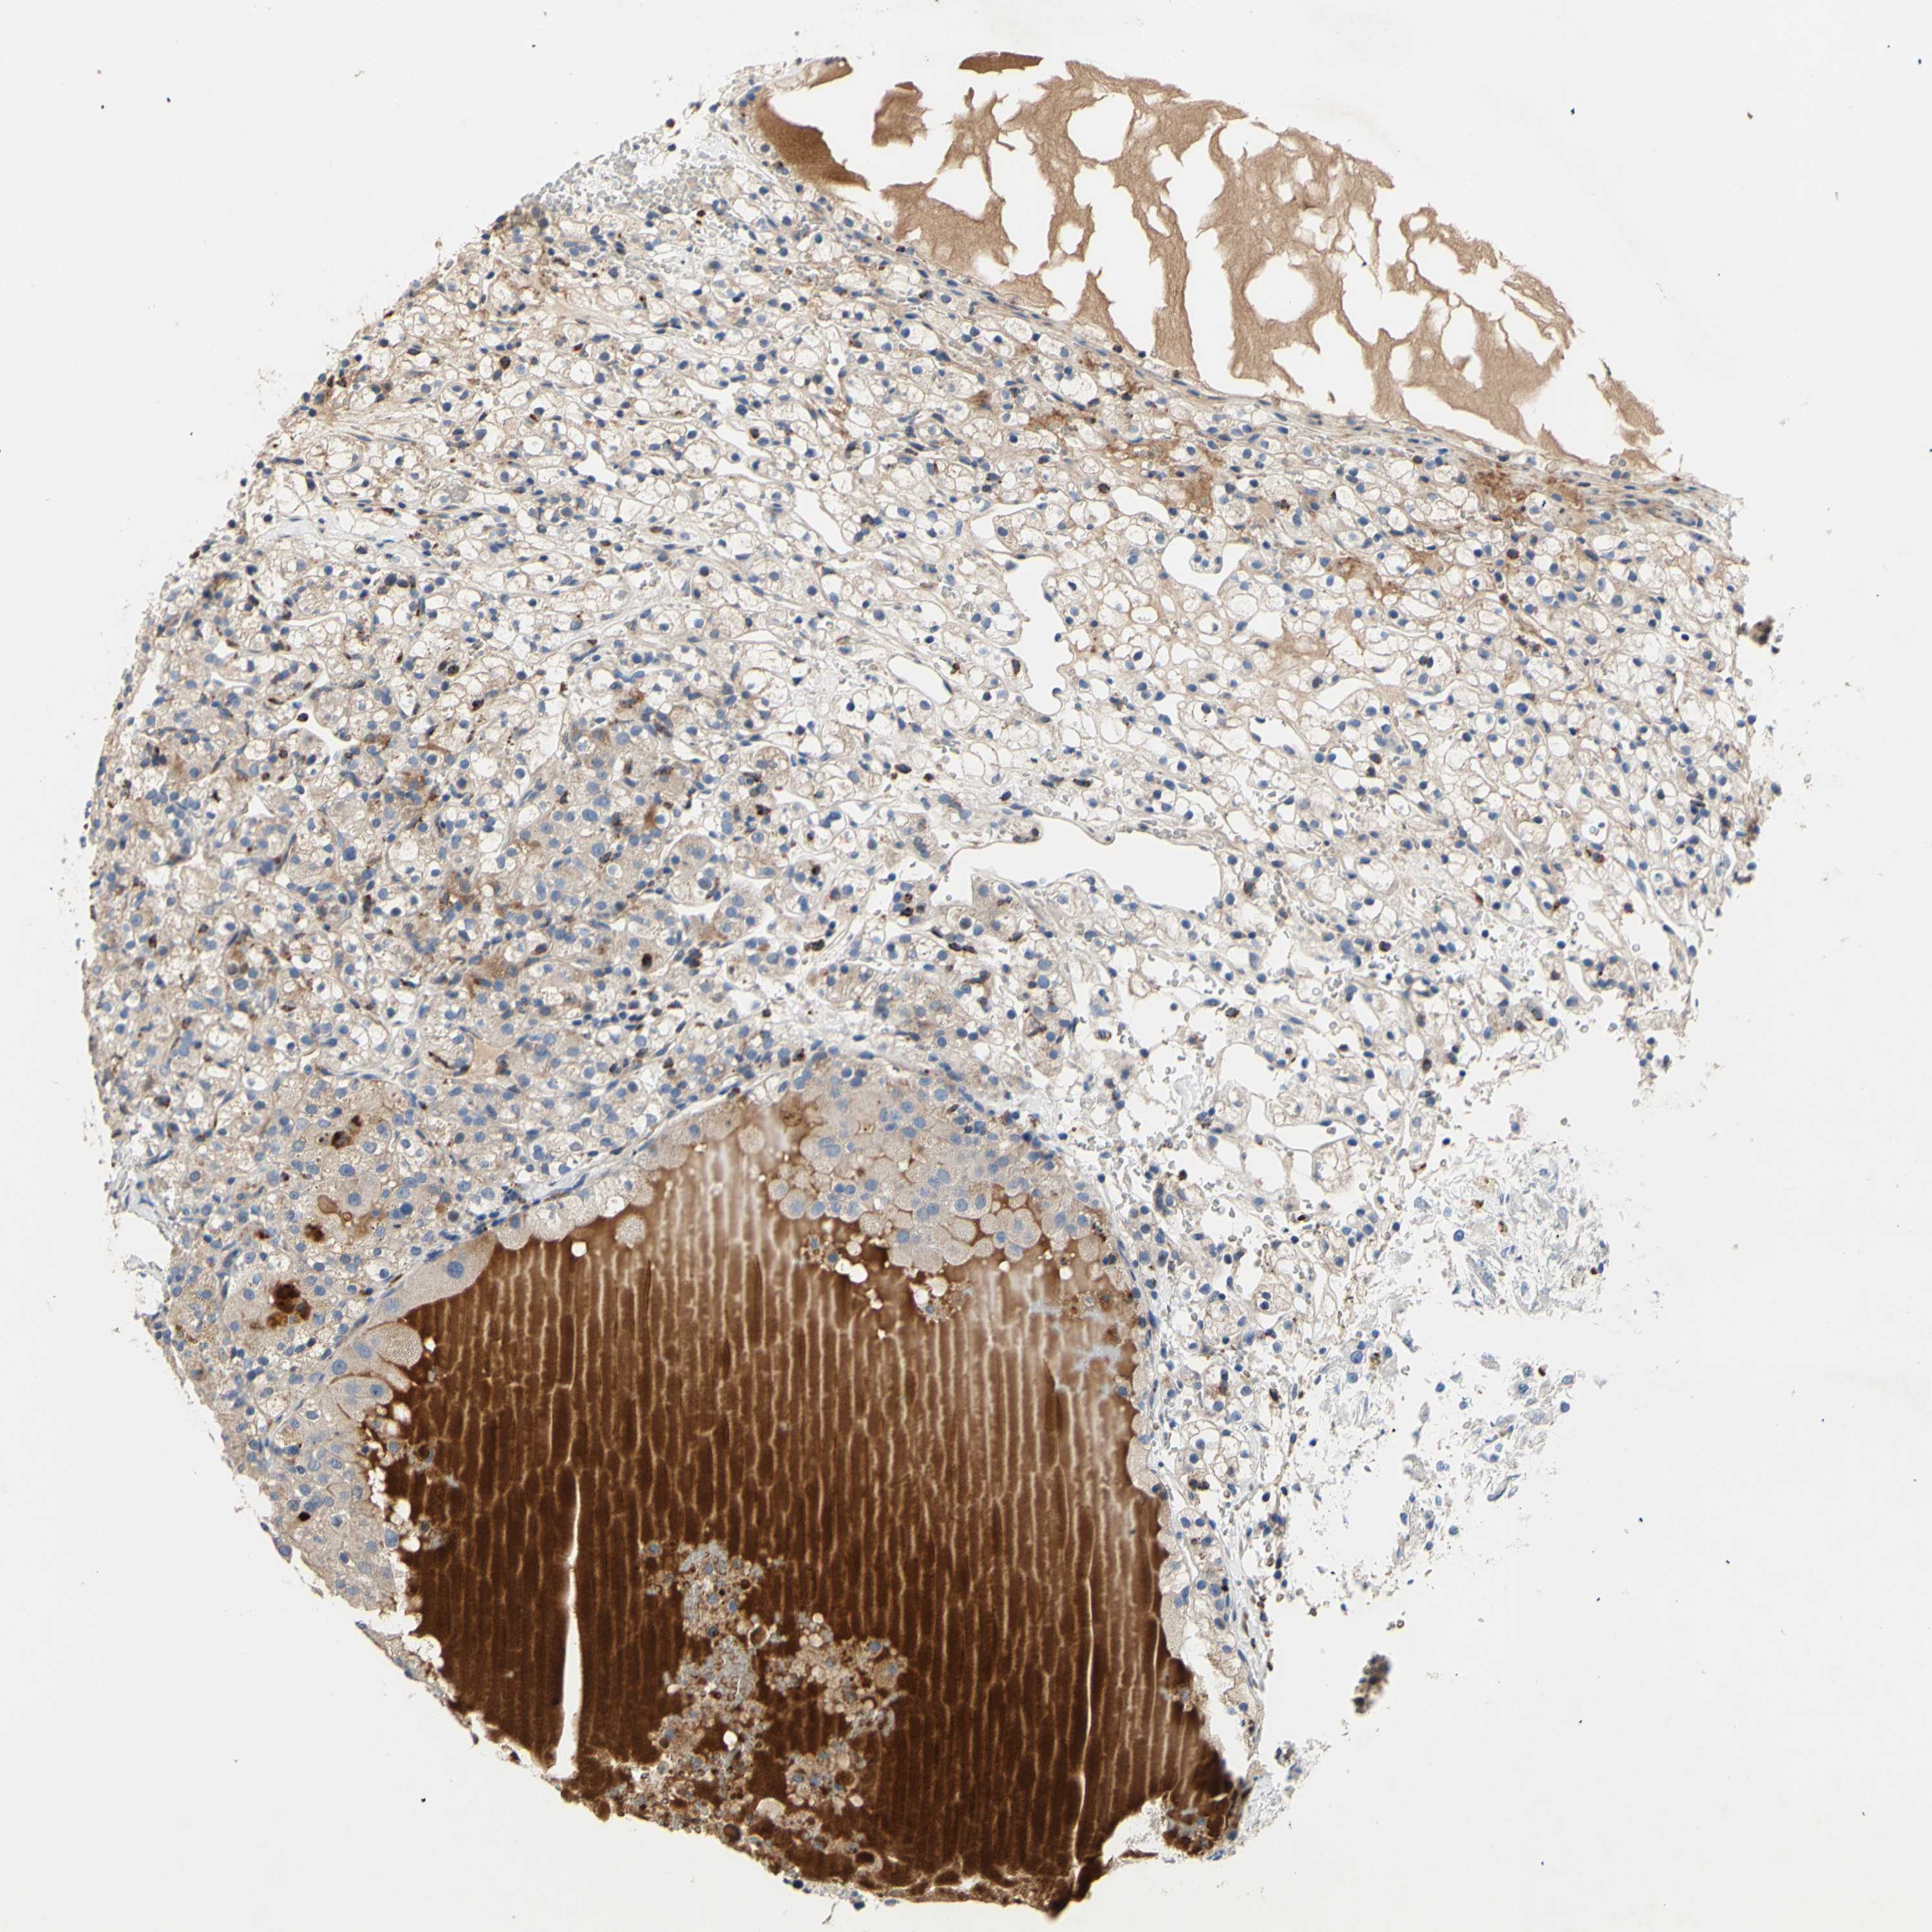

CANCER RENAL CANCER Show tissue menu

KICH TCGA KIRC TCGA KIRC VALIDATION KIRP TCGA PROTEIN RCC CPTAC PROTEIN EXPRESSION

Renal cancer

Human cancer

Kidney chromophobe

Kidney renal clear cell carcinoma